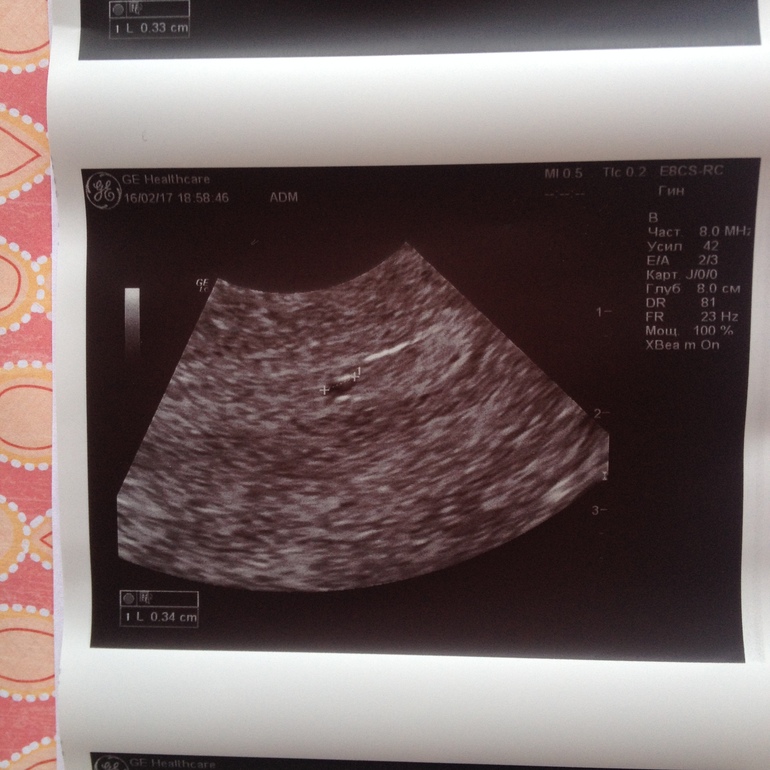

Вчера же вечером на 54 день цикла, после очередного яркого теста на овуляцию поехала на узи, узнать когда же она произойдёт.

На узи доминантного не нашли, эндометрий 11 мм., желтое тело нашли еле-еле и то, через живот,а не на внутреннем узи. Жидкость есть.

Врач долго меня смотрела, в итоге нашли пузырёк в матке.) 3.4 мм.

По пузырьку, срок 1.5 недели от зачатия.